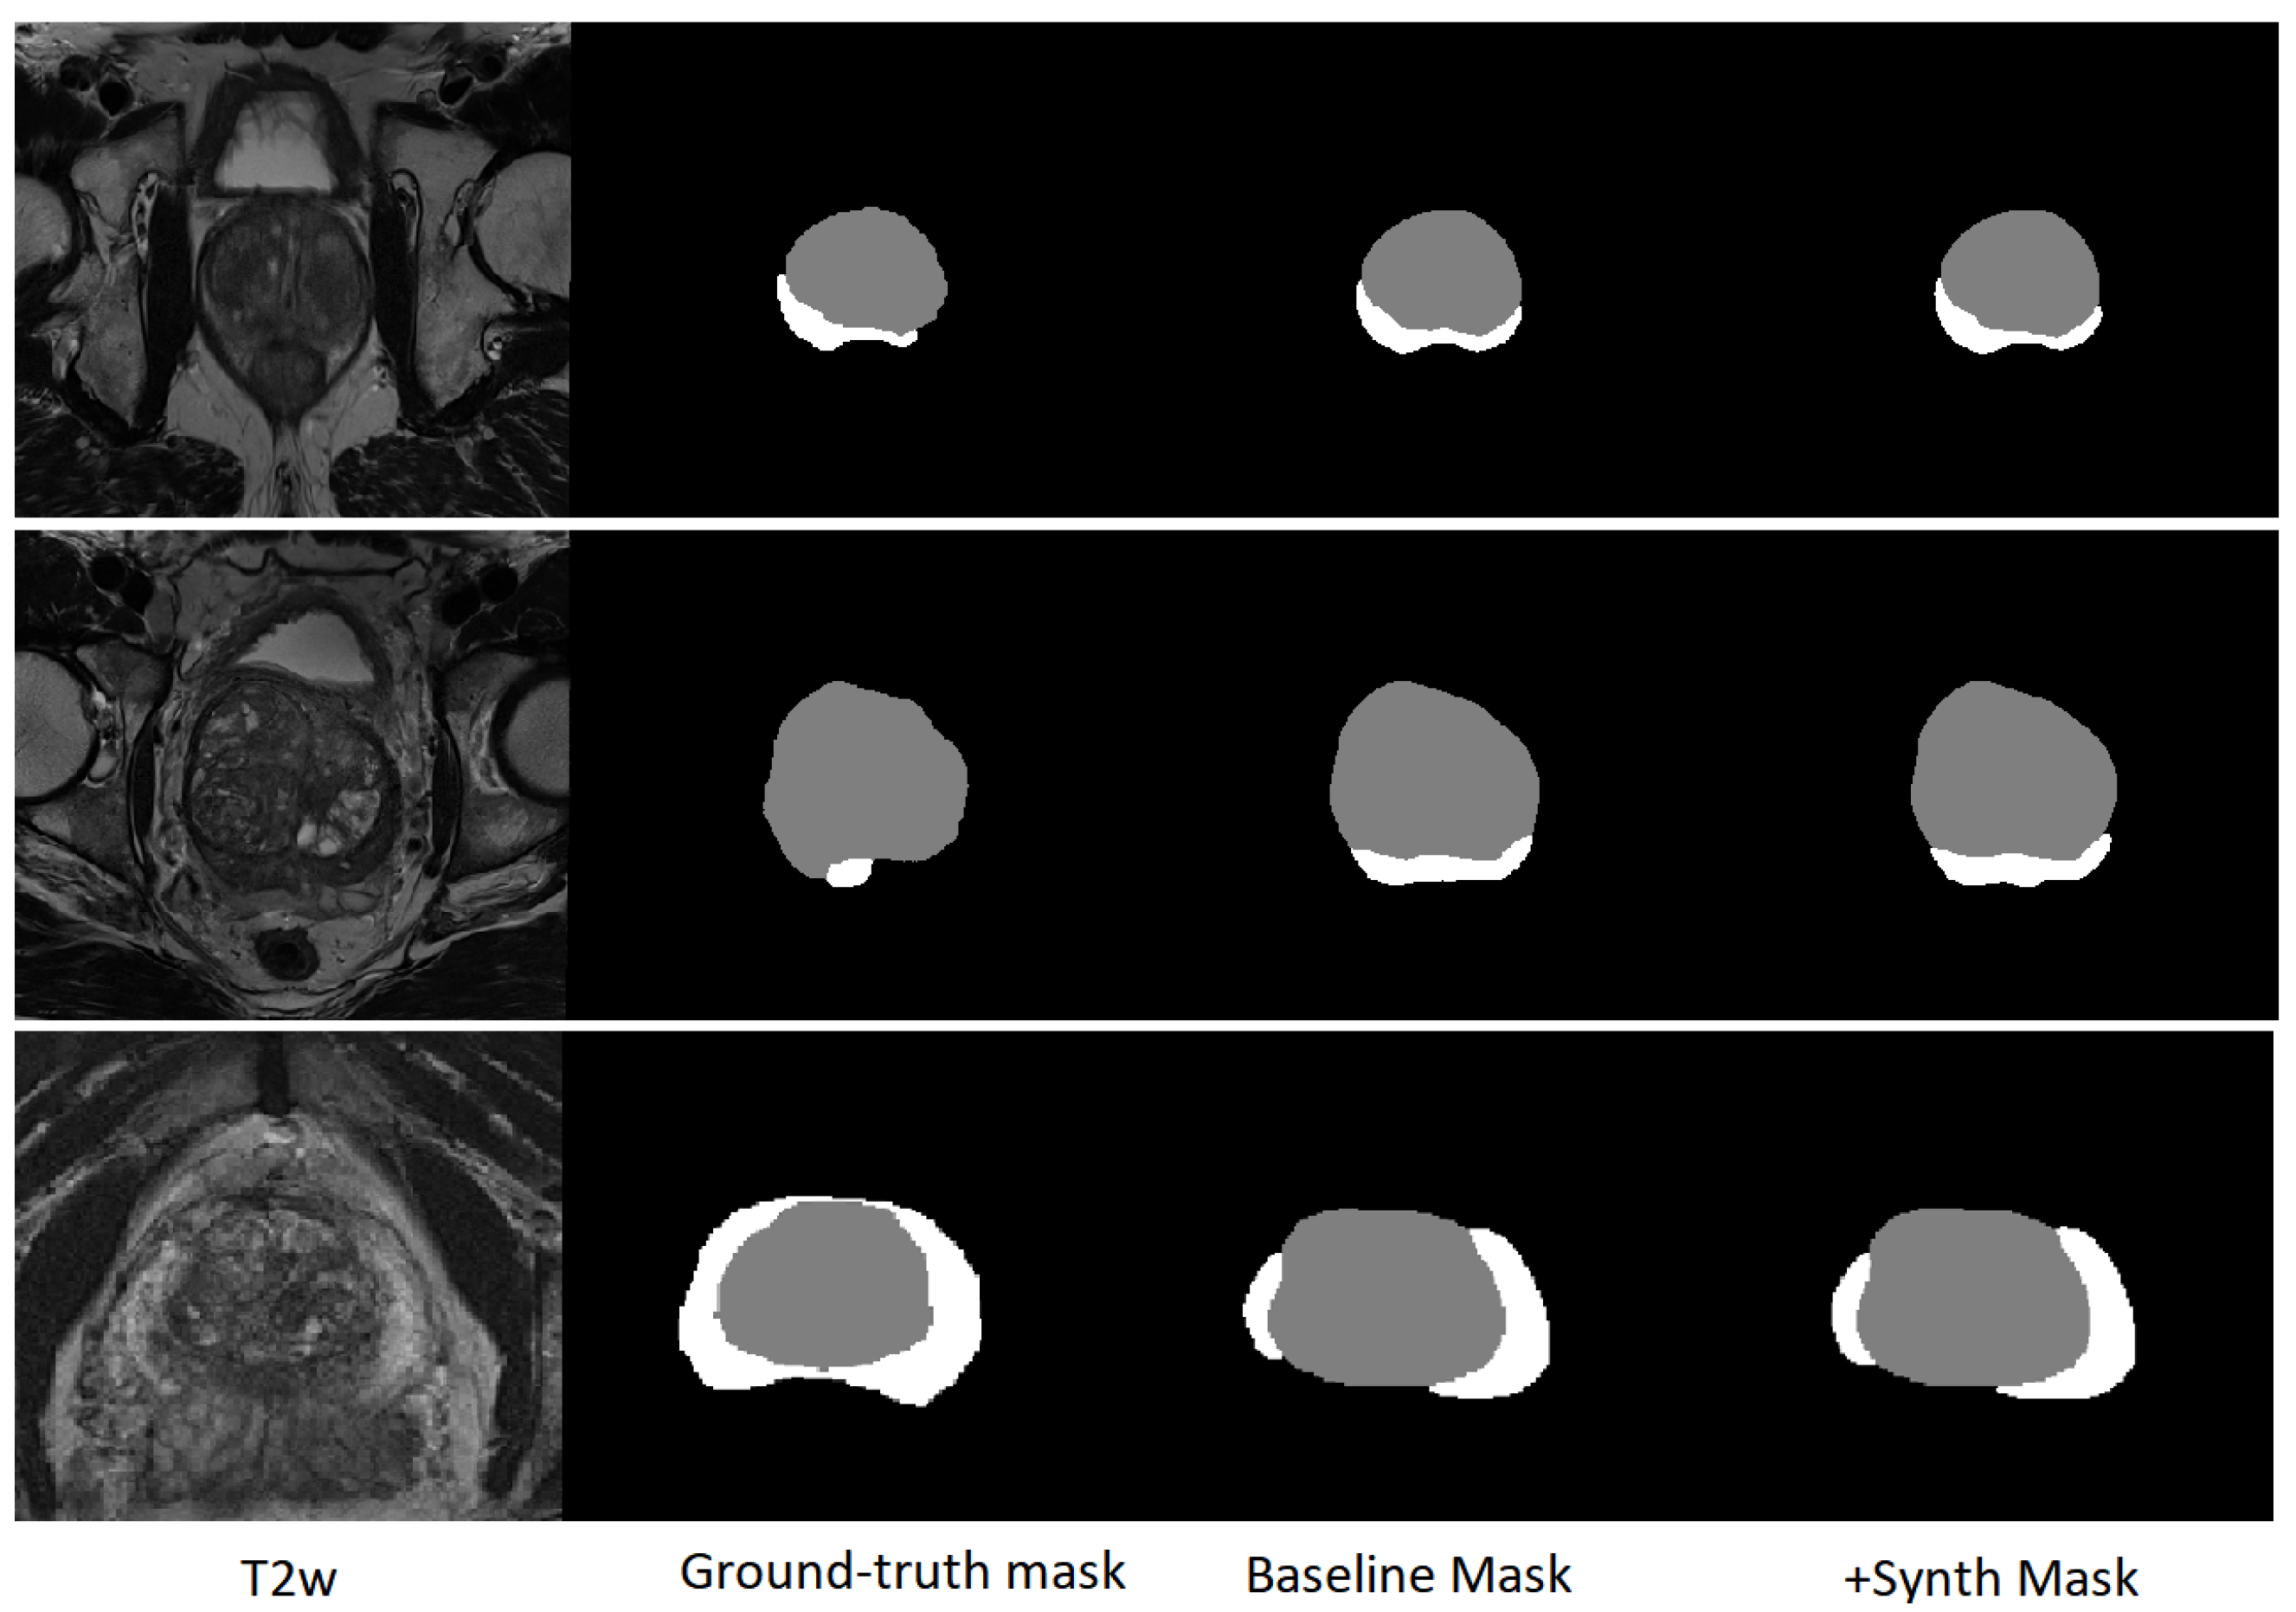

Incorporating synthetic data yielded segmentation performance statistically indistinguishable from the baseline model trained on real data alone. Preservation of performance across both anatomical regions supports that volumetric generation maintains structural integrity and anatomically relevant boundaries. Representative segmentation predictions are shown in Figure 3, together with the corresponding T2W images and ground-truth masks. Visually, the delineations produced by the baseline and +Synth models are highly consistent across cases, with only minor local differences (e.g., slightly improved peripheral zone coverage in the bottom example), in agreement with the quantitative results. These findings provide task-based validation that the synthetic images preserve segmentation-relevant features consistent with real prostate MRI.

Figure 3. Representative segmentation predictions on test cases. From left to right: T2W image, ground-truth mask, baseline nnU-Net v2 prediction (trained on real data only), and prediction after fine-tuning with 750 synthetic T2W images (+Synth).